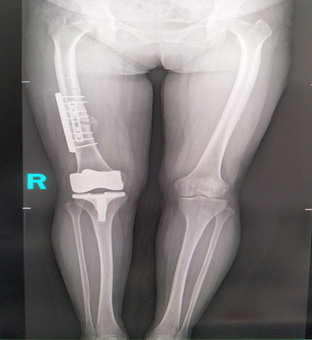

1、判斷下肢力線,主要用于膝關(guān)節(jié)內(nèi)外翻畸形的測(cè)量,能比較準(zhǔn)確地反應(yīng)骨結(jié)構(gòu)異常和軟組織不平衡對(duì)膝關(guān)節(jié)內(nèi)外翻的最終影響。對(duì)膝關(guān)節(jié)置換的X線評(píng)估尤為重要。

這一DR全景成像技術(shù)是基于全自動(dòng)拼接技術(shù),能夠有效地滿足臨床應(yīng)用的需要,相對(duì)既往技術(shù)水平來說,這一技術(shù)是一個(gè)很大的突破。

01、可以精確測(cè)量雙下肢的長度;

02、可以更好地判斷下肢力線和解剖學(xué)角度;